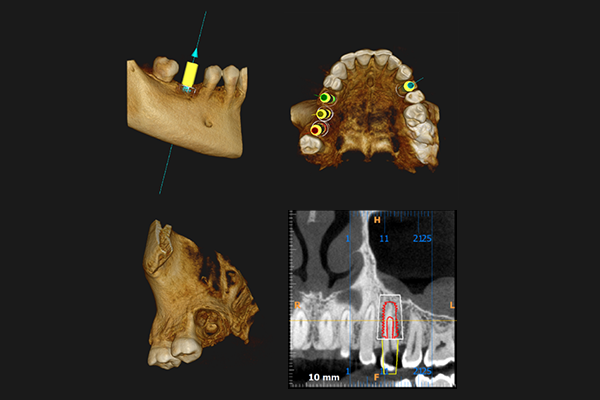

Cone Beam Computed Tomography

CBCT (Cone Beam Computed Tomography) had been introduced in Europe way back in 1996 and in the USA in the early 2000s. It has, since then, been a revolutionary invention that changed the world's dental radiology panorama. In the past couple of years, it has made its advent in the Indian market. With its various benefits for both dentists and patients, CBCT has been quite gripped the diagnostic beat in Kolkata. CBCT has become a part and parcel of dentistry and has thus, significantly improved quality and excellence of dental treatment.